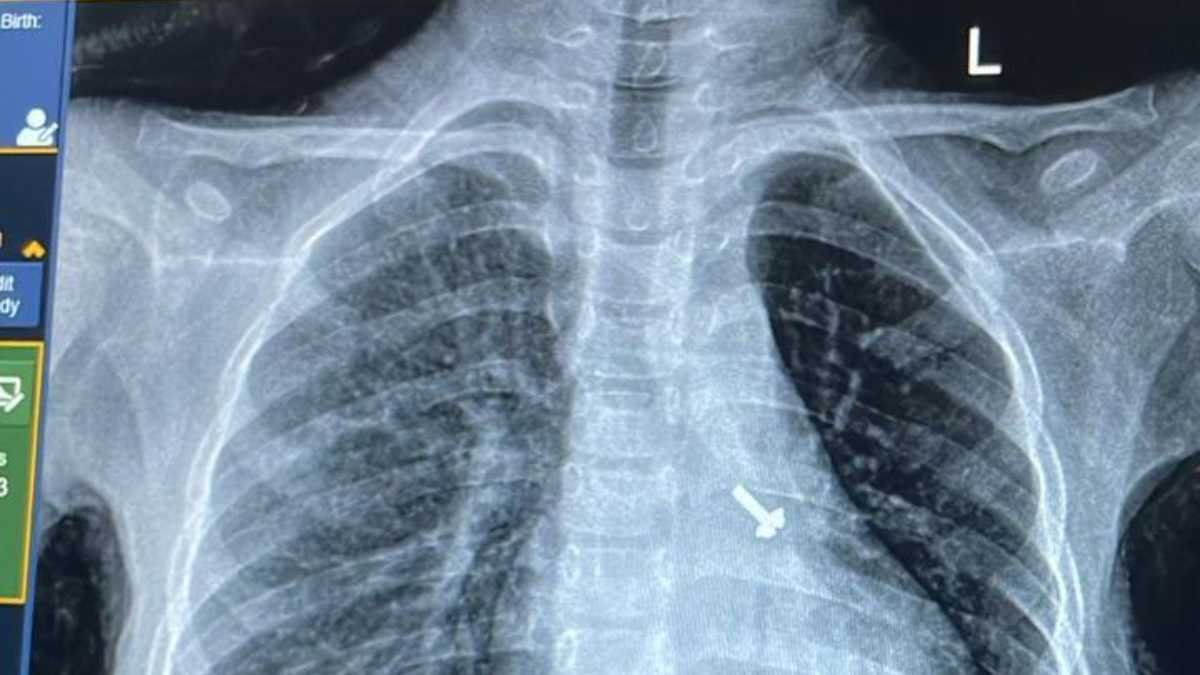

बालरोग विशेषज्ञ डॉ. व्यास कुमार राठौड़ के मुताबिक बच्चे की कुछ प्रारंभिक जांचें कराई गईं, जिसमें उसकी छाती के एक्स-रे एवं सीटी स्कैन में बच्चे के फेफड़े में एक पेंच दिखाई दिया है । इस विषय में चिकित्सक द्वारा बच्चे के अभिभावकों से पूछे जाने पर उन्हें बताया गया कि बच्चे ने घर में खेल-खेल में पेंच निगल लिया, जिसका पता परिजनों को नहीं लग पाया ।

बाल रोग विभाग से बच्चे से संबंधित उक्त जानकारी मिलने पर पल्मोनरी मेडिसिन विभाग की विशेषज्ञ चिकित्सक आचार्य डॉ. रुचि दुआ के साथ उनकी टीम के सदस्य डॉ. प्रखर शर्मा, डॉ. दीपांश गुप्ता, डॉ. ऋत्विक सिंगला, डॉ. अश्वथी साबू के अलावा बाल रोग विभाग के विशेषज्ञ डॉ. व्यास कुमार राठौड़, डॉ. मान सिंह, डॉ. श्रीजन, एनेस्थीसिया विभाग के विशेषज्ञ डॉ. प्रियंका गुप्ता, डॉ. रीना , डॉ. अजहर, बाल शल्य चिकित्सा विभाग की विशेषज्ञ डॉ. शौर्या व रेडियोलॉजी विभाग के विशेषज्ञ डॉ. राहुल देव की देखरेख में पल्मोनरी मेडिसिन विभाग की ब्रोकोस्कोपी प्रयोगशाला में Flexible Bronchoscopy के माध्यम से बच्चे के फेफड़े से सफलतापूर्वक पेंच को निकाल लिया गया । अब बच्चा पूरी तरह से स्वस्थ एवं सुरक्षित है ।